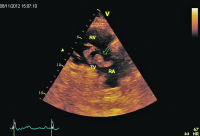

Rechtsventrikulärer Einflusstrakt

Abbildung 2: Parasternale Darstellung des rechtsventrikulären Einflusstraktes. Flottierender Thrombus (Pfeil) im RA. Dilatierter und hypokontraktiler RV. RA: rechter Vorhof; RV: rechter Ventrikel; TV: Trikuspidalklappe.